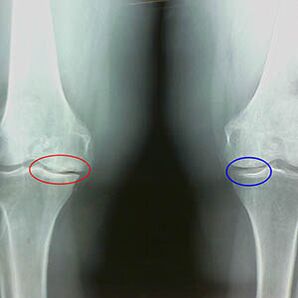

Bestimmung des Arthrosegrades erfolgt durch X -RayAufdeckung der Teilnahme am pathologischen Prozess von Knochenstrukturen. Ihre Veränderung zeigt, dass das Muskelsystem seit 5 bis 10 Jahren ein Ungleichgewicht hat. In der Regel Menschen Für mehrere Jahre erleben sie schmerzende Schmerzen.

Frühe X -Strahlenmerkmale der zweiten Stufe der Kniearthrose:

- die spitzen Kanten der internen Tuberkeln auf der Tibia, an denen das Kreuz -verdrängte Band befestigt ist;

- Verengung der gemeinsamen Lücke auf der medialen Seite;

- Die spitzen Kanten der Knochenkondylus auf den medialen Seiten, seltener in seitlich - abhängig von der Entwicklung des Valgus oder der Verformung der Variorverbindung.

Für die zweite Stufe in Larsen Die Verengung der gemeinsamen Lücke um mehr als 50% ist charakteristischDies kann jedoch nur in der Dynamik oder im Vergleich mit einem Ununterbrochenen von Gelenke überprüft werden.

Das Röntgenbild zeigt das Vorhandensein von Osteophyten, eine Änderung des Raums zwischen der Femur- und Tibia -Knochen, was den Knorpelverlust im Knie anzeigt. Manchmal zeigt das X -Strahlen der Kniegelenke signifikante Anzeichen von Knorpelverschleiß, aber Patienten haben keine signifikanten Schmerzen.Im Gegenteil kann die Arthrose der ersten Stufe die Funktion des Knies störenda ist die Ursache des Schmerzes hypotonische Muskeln.